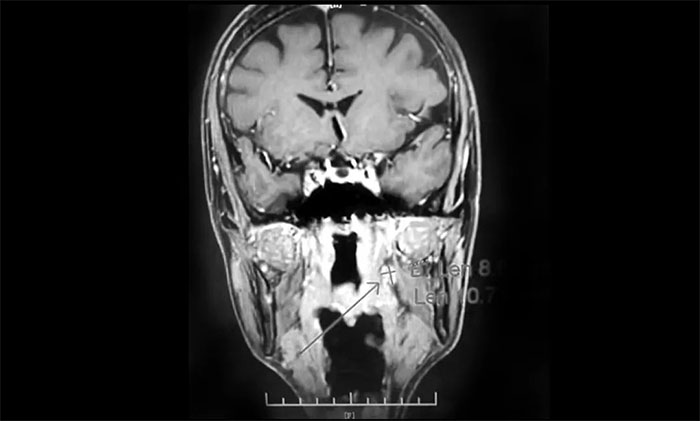

經MDT多學科會診評估,制定以放療為主的同步放化療方案。治療後複查MRI,患者左側鼻咽部實性佔位較前治療明顯減小;原左側下頜腺區、咽旁腫大淋巴結已基本吸收好轉,左頸部腫大淋巴結較前明顯縮小。

▲ 放療後複查MRI,腫瘤佔位較前明顯減小